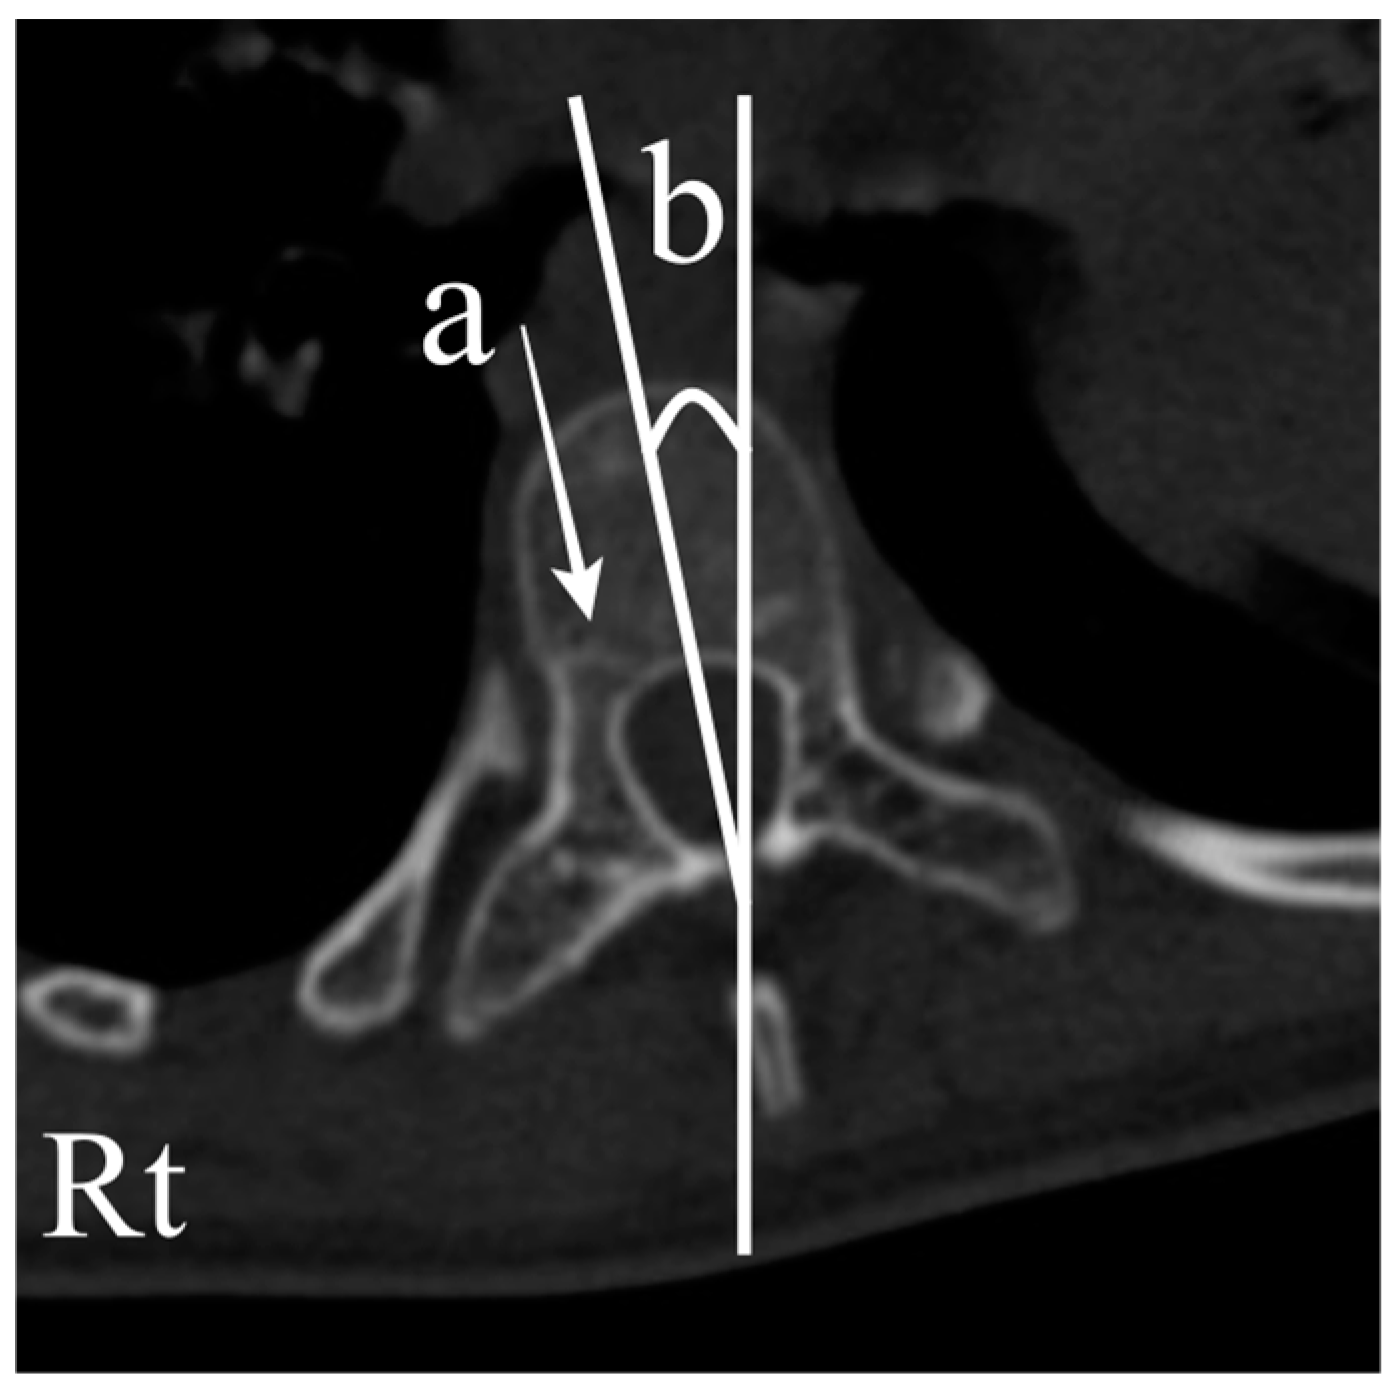

In total, 102 vertebrae with CP scoliosis and 96 vertebrae with AIS were measured. Pedicle diameter (PD), chord length (CL), and vertebral body rotation (VBR) were evaluated one level above the apex, one level below the apex, and at the apex using a reconstructed CT scan [14,17,18,19]. PD was measured in the isthmus region, where the medial and lateral middle cortical borders were the narrowest. The CL was measured as the distance between the posterior cortical entry point of the pedicle and the anterior vertebral cortex in line with the axis of the pedicle. VBR was measured as the angle between the vertical line and the line that bisects the vertebral body (Figure 2). Additionally, the presence of neurocentral synchondroses was investigated (Figure 3) [20,21].

Figure 3. Exemplar vertebra with neurocentral synchondrosis (a) and a vertebral body rotation toward the right side (b).